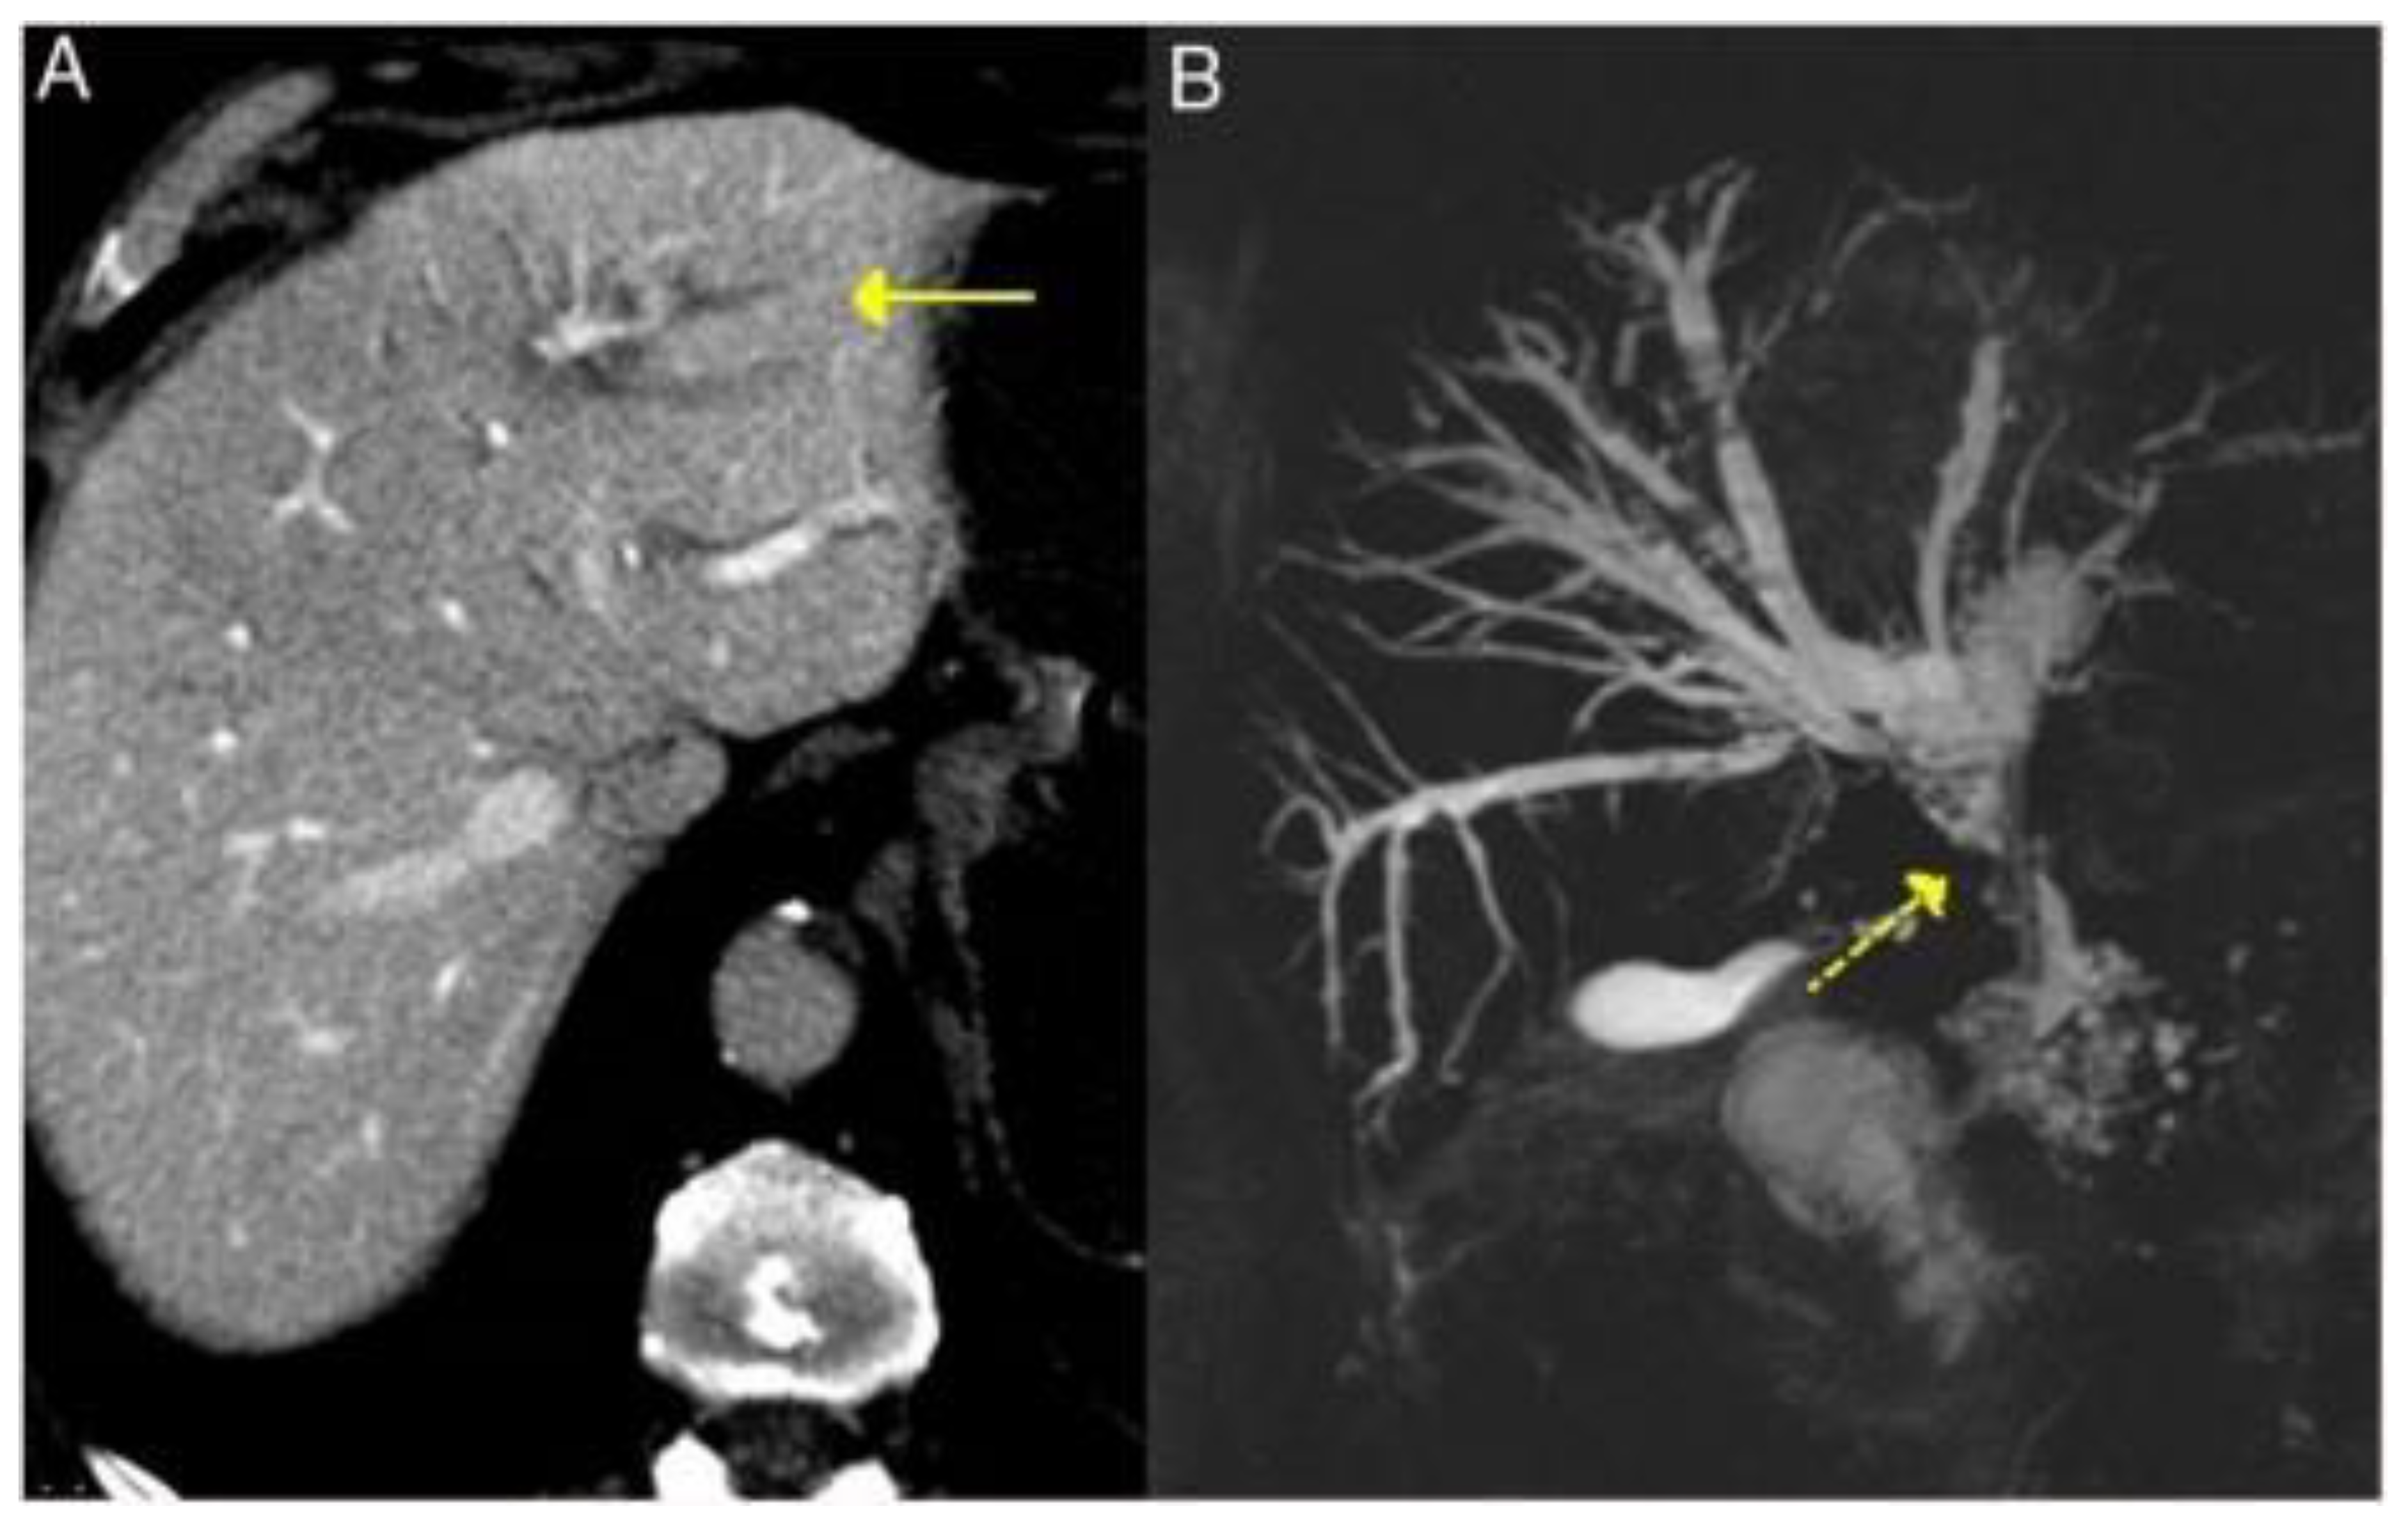

3.2.4. Liver and Bile Ducts